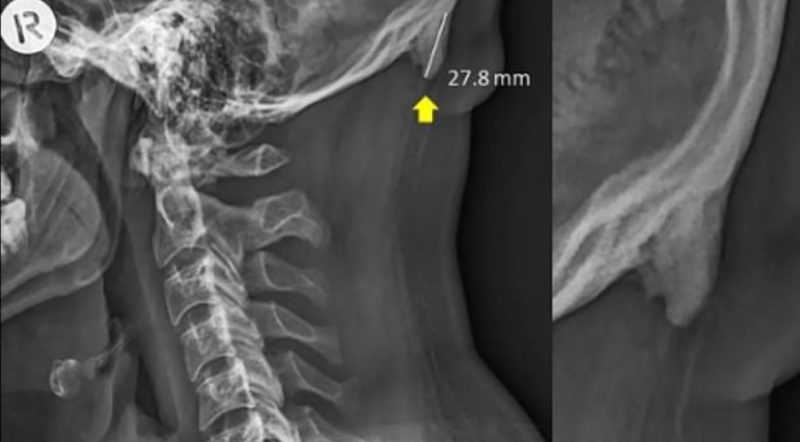

Pasar tanto tiempo con la mirada hacia abajo produce tal cambio en la postura que nuestra estructura ósea trata de adaptarse para sostener mejor nuestra cabeza. La prueba está en las imágenes de rayos X publicadas por investigadores australianos que muestran que debido a la forma en que estamos constantemente encorvados con nuestros teléfonos, los cráneos desarrollaron un crecimiento óseo adicional. La cabeza de adulto promedio puede pesar alrededor de 5 kilogramos.

Según el estudio, un número creciente de personas, especialmente los jóvenes de entre 18 y 30 años, tienen crecimientos llamados protuberancias occipitales externas agrandadas, que se encuentran en la parte inferior del cráneo. “Los trastornos musculoesqueléticos relacionados con la mala postura durante el uso de computadoras y tablets se investigaron de forma exhaustiva y se identificaron como un factor de riesgo para el desarrollo de síntomas relacionados en el cuello, los hombros y los antebrazos “, argumentan.